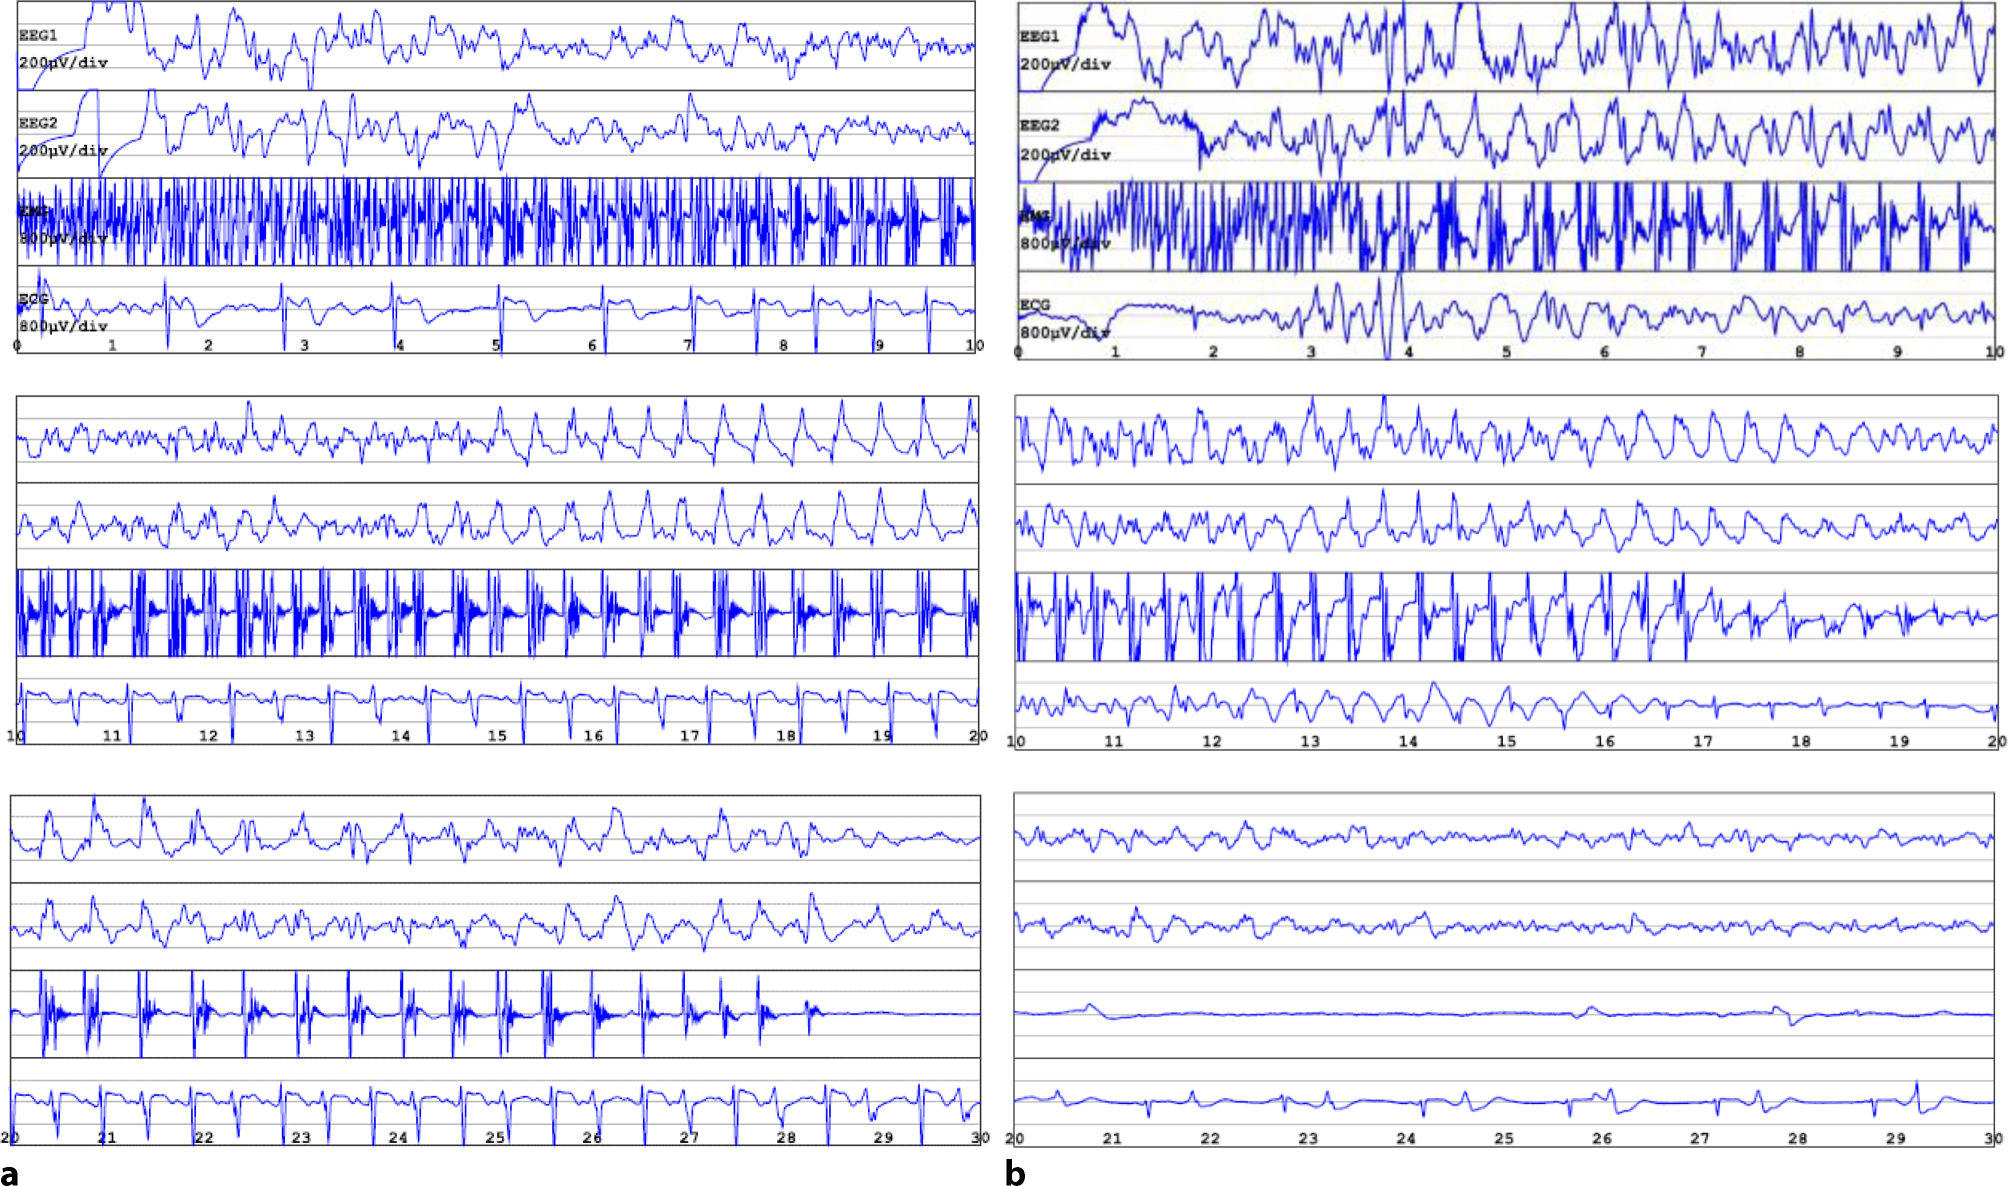

Fig. 1

Electroconvulsive therapy (ECT) reports from two different treatment sessions. a Spontaneous generalized tonic-clonic seizure after administration of etomidate, 20 mg: intermittent spike activity on the background of low beta and theta activity turning into spike epileptic activity of low amplitude, slow frequency, and transition to medium amplitude (15 to 20 s), medium frequency, with clear seizure termination (second 29) and poor suppression. b Induced seizure with 140% energy setting and anesthetic thiopental, 400 mg: intermittent spike activity turns into spike epileptic activity of medium amplitude, medium frequency, with less clear seizure termination and poor suppression. EEG 1 and 2 electroencephalogram in right and left channel, respectively. x‑axis time in seconds, y‑axis amplitude in µV. EMG electromyogram. ECG electrocardiogram

The subsequent two ECT treatments, switched back to thiopental 400 mg, showed adequate ECT-induced seizures (Fig. 1b). After 12 treatments, the ECT course was discontinued due to insufficient response, documented by a MADRS score of 21 points, indicating clinical improvement but an inadequate response to ECT. Bupropion XR was increased to 300 mg.

To our knowledge, this is the first case of a recorded spontaneous seizure after etomidate administration prior to ECT. Patients with a history of epilepsy and/or cerebral cortical lesions appear to be at risk of developing seizures after etomidate administration, while our patient had no identifiable risk factors or known family history of neurological disorders. The EEG after the spontaneous seizure revealed moderate diffuse cerebral dysfunction, without typical signs of epileptic activity. Interestingly, the neuronal activity (Fig. 1a) in the spontaneous seizure under etomidate seems to be comparable to the ECT-induced seizure under thiopental anesthesia (Fig. 1b). The peripheral seizure activity lasted longer, and synchronization and seizure termination seemed to be better in the spontaneous event than in ECT stimulation. Seizure suppression and termination were similar in both convulsions. The dose of etomidate used in our case is comparable to the other cases; administering an additional dose did not result in seizure cessation [4, 5, 10].